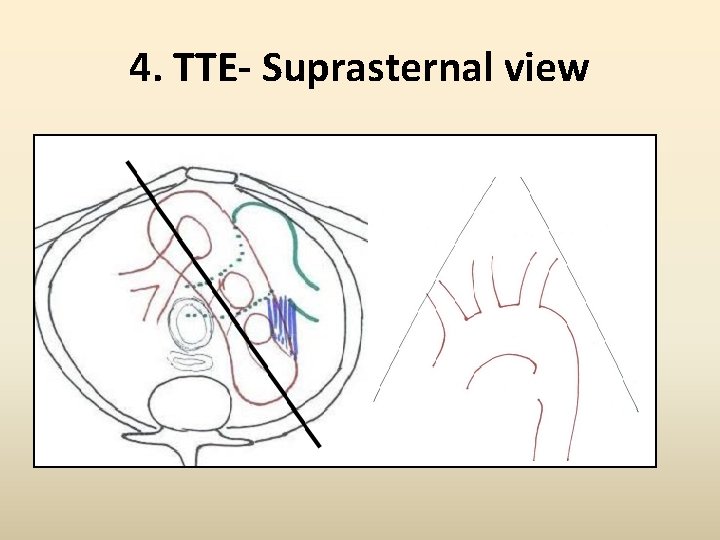

4. TTE- Suprasternal view